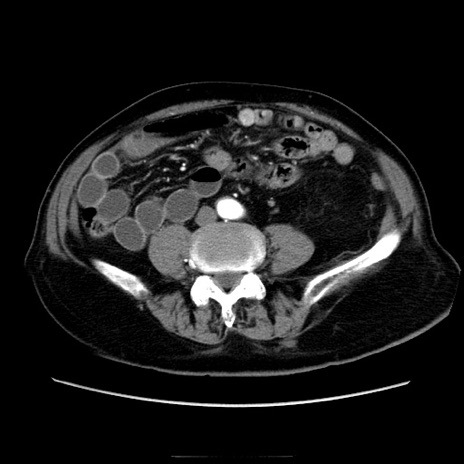

症例21(横断像)

【症例】70歳代男性

【現病歴】肝硬変・肝細胞癌にてかかりつけの方。約9時間前に食後より腹痛出現。症状が徐々に増悪し、嘔吐出現したため来院。

【既往歴】肝硬変、肝細胞癌(RFA、TACE後)

【身体所見】意識清明、表情苦悶様、BT 36℃、BP 129/78mmHg、P 88bpm、SpO2 97%(RA)、右上腹部から心窩部にかけて圧痛あり、反跳痛なし、筋性防御あり。

【データ】WBC 5800、CRP 0.16